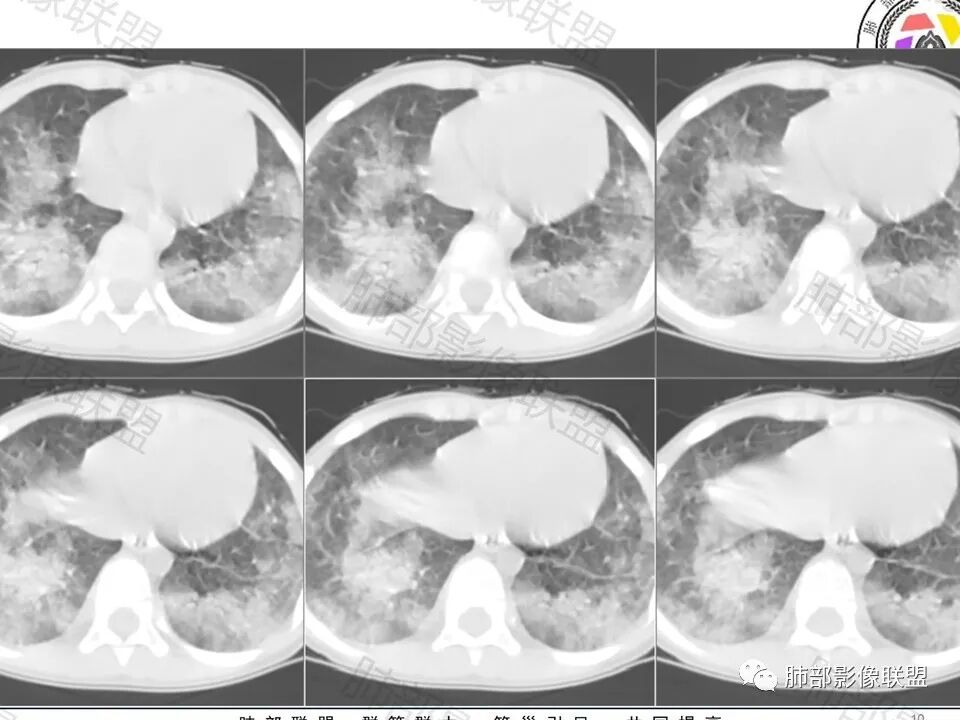

一.双肺广泛磨玻璃片影,边界可分辨,状如“补丁”,背侧分布为主,但胸膜下存在间隙。偶见小结节影。不符合常见的肺水肿及间质性肺病等。结合临床表现,是可以符合肺出血改变的,尽管影像尚需排除其他。

这里强调双肺的广泛性和弥漫性。

儿童患者,贫血,发热,双肺弥漫性磨玻璃影,未见支气管空气征,不支持炎性病变,患者有反复出血病史,考虑双肺弥漫性出血。

4岁,有地中海贫血,鼻出血,胃出血,发热咳嗽2天,双肺野弥漫分布磨玻璃实变影,多靠近外带胸膜下,边界模糊,有的磨玻璃影较淡,考虑含铁血黄素沉着症。肺水肿不像。

4岁,有地中海贫血,鼻出血,胃出血,发热咳嗽2天,双肺野弥漫分布磨玻璃实变影,多靠近外带胸膜下,边界模糊,有的磨玻璃影较淡,支持考虑弥漫性肺泡出血

4岁患儿,鼻胃出血,慢性病程,重度贫血,两肺多发磨玻璃及实变影,以两下肺分布为主,沿支气管血管束分布,两肺实变内可见粗细不均血管影,综和考虑支持含铁血红素沉着症,其次考虑弥漫性肺泡出血